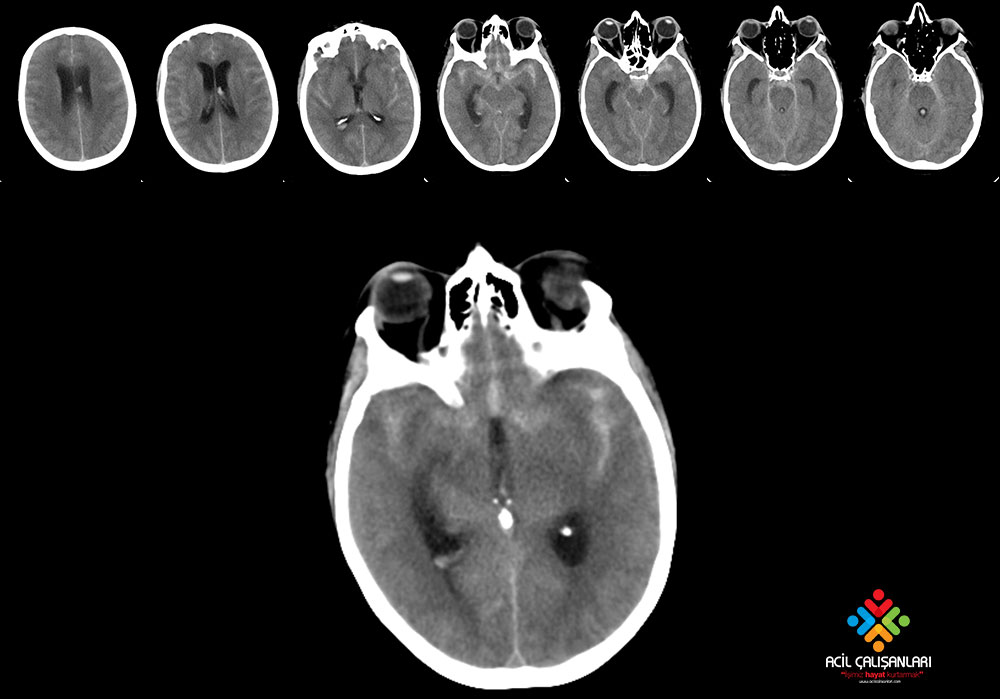

46 yaşında erkek hasta şiddetli baş ağrısı ve bilinç değişikliği nedeniyle acil servise başvuruyor. Acil servis hekimi hastayı değerlendirdiğinde: baş ağrısının ani başladığını, çok şiddetli olduğunu ve sonrasında hastada bilinç değişikli geliştiğini öğreniyor. Hastanın genel durumu kötü, oryente koopere değil, GKS 7, kan basıncı 240/100 mmHg, kalp hızı 88 atım/dk, oda havasında oksijen satürasyonu % 96 ve ateşi 36,5'C olarak saptanıyor. Fizik muayenede nöromotor net değerlendirilemiyor diğer sistemler doğal olarak değerlendiriyor. Acil hekimi hemen hastayı entübe ediyor, hastanda kan testi istiyor ve sonrasına aşağıda görüldüğü gibi kontrastsız beyin bt çektiriyor. Bu hasta için acil serviste en uygun tedavi yaklaşımı ne olmalıdır?

Subaraknoid kanama (SAK), kanın beyin omurilik sıvısının (BOS) bulunduğu pial ve araknoid membranlar arasındaki subaraknoid boşluğa (ekstravazasyon) kanın geçmesi durumudur. Travmatik veya spontan oluşabilir. En yaygın olanı kafa travması sonucunda travmatik meydana gelir. Travmatik olmayan subaraknoid kanamalar arteryel nadiren de venöz nedenlere bağlı olarak meydana gelir ve sıklıkla anevrizma rüptürü (% 85) sonucu ortaya çıkar. Orta ve ileri yaş grubunda önemli bir morbidite ve mortalite nedenidir. Anevrizmal SAK hastalarının klasik başvurusu tipik olarak “hayatımın en şiddetli baş ağrısı” olarak tanımlanan ani başlayan şiddetli bir baş ağrısıdır. Bu tür baş ağrısı olan her hasta SAK için mutlak değerlendirilmelidir. Baş ağrısı genellikle izole bir bulgudur. Hastalar çoğunlukla baş ağrısını “yıldırım çarpması” (thunderclap) şeklinde ani başlayan maksimum şiddete hızlı ulaşan şiddetli bir baş ağrısını şeklinde ifade ederler.